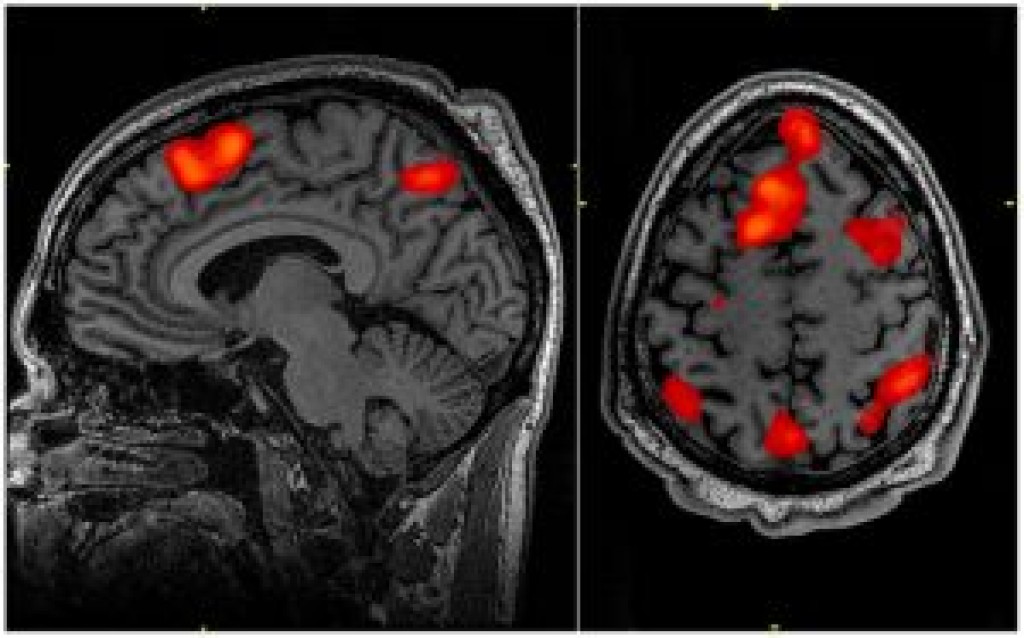

Causada pela perda de células em uma parte do cérebro denominada gânglios da base, ela compromete as capacidades motoras, através de movimentos involuntários dos membros inferiores e superiores.